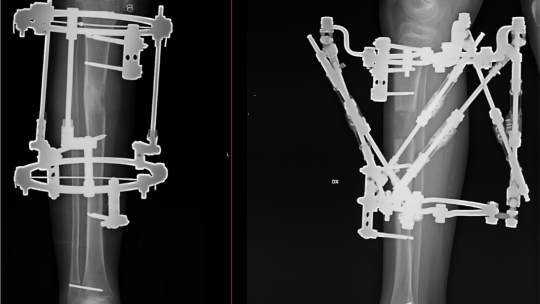

Ekstremitāšu asimetrijas un deformāciju korekcija

Taisnas kājas, viegla gaita, stalta stāja ir ne tikai skaistuma etalons, bet galvenokārt veselības balsts. Ekstremitāšu izliekumam, garumam un simetrijai ir funkcionāla nozīme.